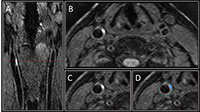

For the new study, researchers used 3-D MRI to study the carotid arteries for evidence of intraplaque hemorrhage (IPH), an indicator of advanced atherosclerotic disease.

Dr. Maraj and colleagues focused their study on people with diabetes, a group already facing a significantly increased risk of strokes with worse outcomes than the non-diabetic population. They used 3-D MRI to investigate the prevalence of carotid IPH in 159 asymptomatic type 2 diabetic patients, average age 63, recruited from a dietary trial between 2010 and 2013.

Of the 159 patients imaged, 37, or 23.3 percent, had IPH in at least one carotid artery. Five of the 37 patients had IPH in both carotid arteries. IPH was found in the absence of carotid artery stenosis, or narrowing, and was associated with an increased carotid artery wall volume as measured by 3-D MRI.

While 2-D MRI has been used for more than a decade to identify and characterize carotid artery plaques, the 3-D method brings an extra level of imaging power, Dr. Maraj noted.

"The advantage of 3-D MRI is you can image the entire carotid artery and pinpoint the area of interest over a shorter period of time compared with multiple 2-D sequences," he said.